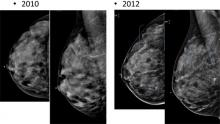

AI is also helping simplify complex tasks and help reduce the reading time on involved exams. One example of this is in 3-D breast tomosythesis with hundreds of images, which is rapidly replacing 2-D mammography, which only produces 4 images. Another example is automated image reconstruction algorithms to significantly reduce manual work. AI also is now being integrated directly into several vendors' imaging systems to speed workflow and improve image quality.